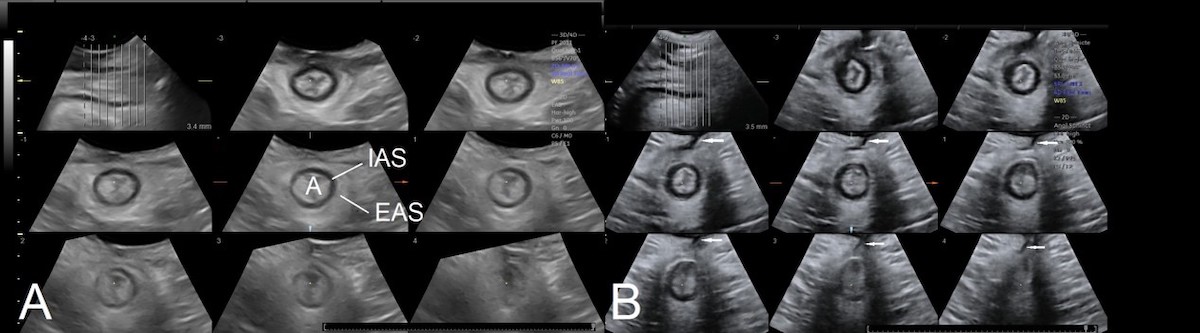

Obstetric anal sphincter injury (OASI) is the main cause of anal sphincter defects. Exoanal ultrasound imaging can facilitate clinical audit in obstetrics, e.g., as regards quality control after episiotomy (Figure 3) (Subramaniam et al 2015), to determine how accurately major perineal tears are diagnosed (Gillor et al 2020) and the quality of OASI repair (Shek et al 2014). With the capability to diagnose maternal birth trauma by translabial ultrasound, maternal birth trauma will likely become a key performance indicator of maternity services in the near future.

Figure 3: Tomographic ultrasound imaging of a normal anal sphincter (A). Image (B) shows an episiotomy (indicated by arrow). The starting point of the episiotomy was located contralateral to the direction of the episiotomy scar. IAS=internal anal sphincter, EAS= external anal sphincter, A=anal canal.